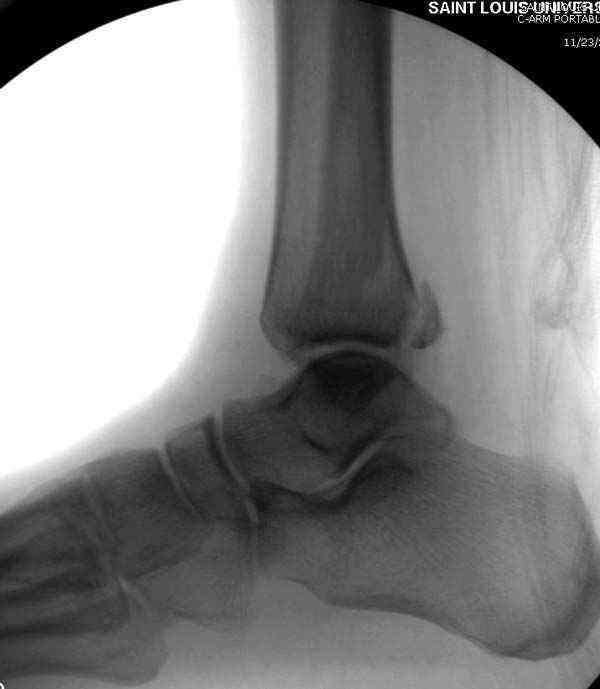

Нет первичных снимков, перелом очень низкий и под большим сомнением диагноз разрыва синдесмоза. Медиальная сторона отрепонирована на "хорошо" и, по-видимому, прорезание проволоки произошло во время операции. Без снимков трудно судить о высоте малоберцовой, а лодыжка находится в варусе. Лагирование получилось, но возле тонких шурупов передне-задний шуруп выглядит немного тяжеловато.

Здесь несколько частных случаев: перелом голеностопа со сравнительными снимками и разрыв синдесмоза, а также медиальная Hook пластина.